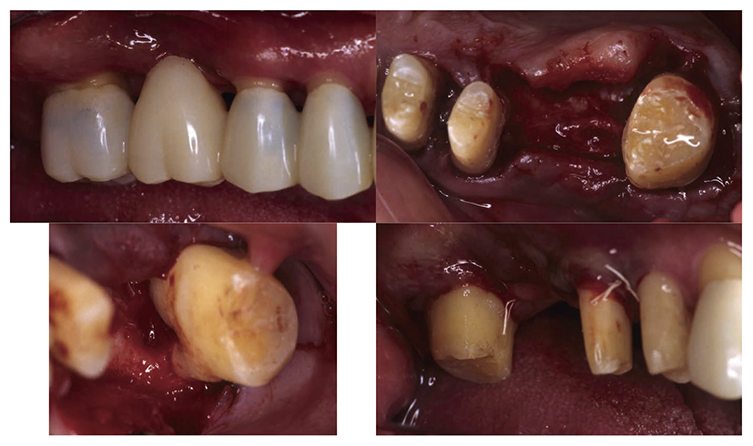

No obvious redness and swelling were present in the marginal gingiva across the full jaw; some blood congestion was however observed. The gingival shape of the anterior teeth in the mandible and maxilla was that of a thick shelf. Significant gingival recession was observed on the mandibular anterior teeth and the buckle side of the left and right maxillary first molar. The dental arch on the maxilla and mandible had a parabolic shape. Teeth separation was however observed between the maxillary central incisors, maxillary right central incisor and lateral incisor, maxillary right canine and first premolar, maxillary left canine and first premolar, and crowding was observed in the mandibular central incisors (Fig.1a).

(Fig.1a) Intraoral photo taken during first visit (June 2007)

At the reevaluation examination after completion of basic periodontal treatment, deep periodontal pockets and grade 2 furcation involvement were observed. Therefore, in April 2010 (age 42), enamel matrix proteins were applied in a procedure for periodontal regeneration (Fig.4),and in June of the same year, gingival flap operation and distal wedge procedure were performed on 27 (Fig.5). For the remaining PD on the lingual side of 36 and 46, due to insufficient keratinized gingiva, the option was to stabilize the condition with SRP.

(Fig.4) Enamel matrix proteins were applied in a procedure for periodontal regeneration in the maxillary left molar (April 1, 2020)

(Fig.5) Gingival flap operation and distal wedge procedure were performed on the maxillary left second molar (June 2010)